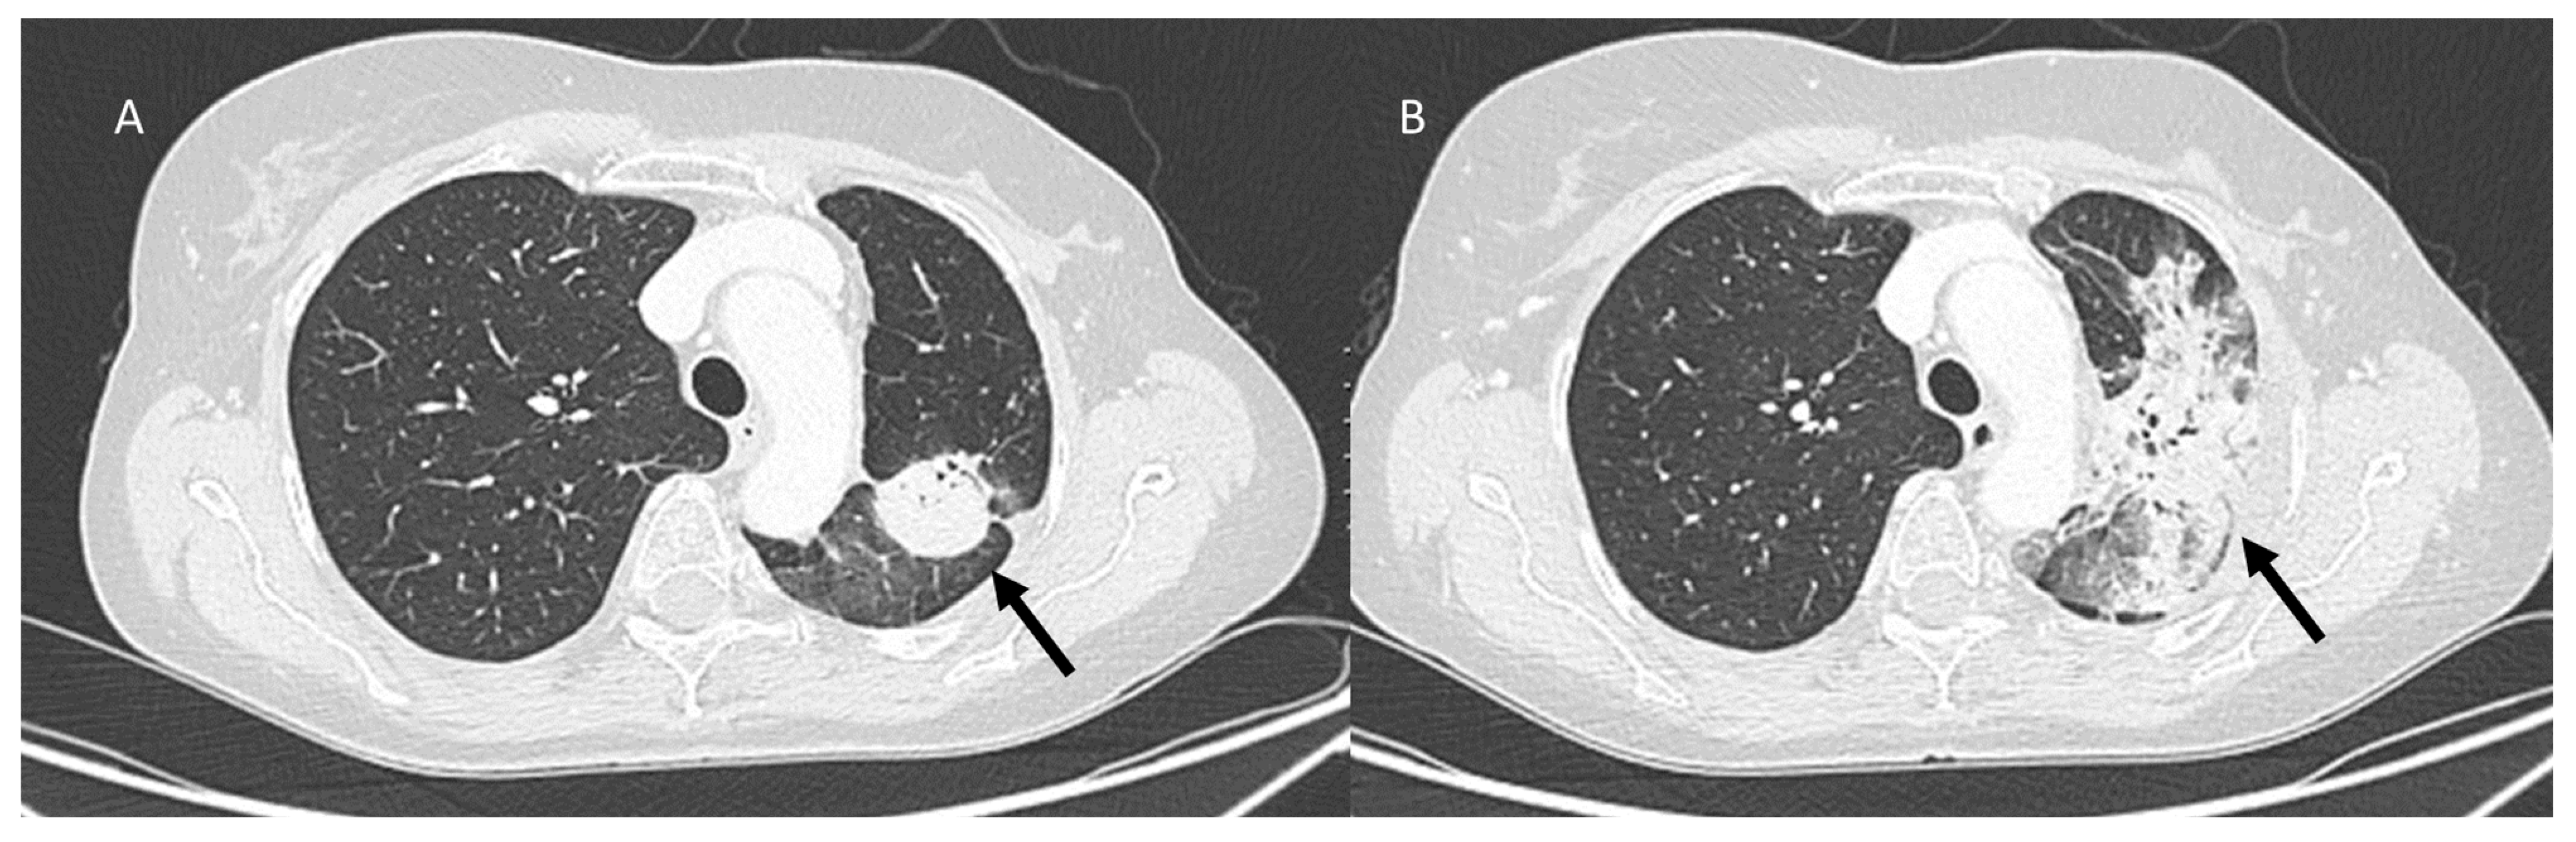

3.5. Progression Disease: Pulmonary Lymphangitis Carcinomatosa

3.6. Machine Learning